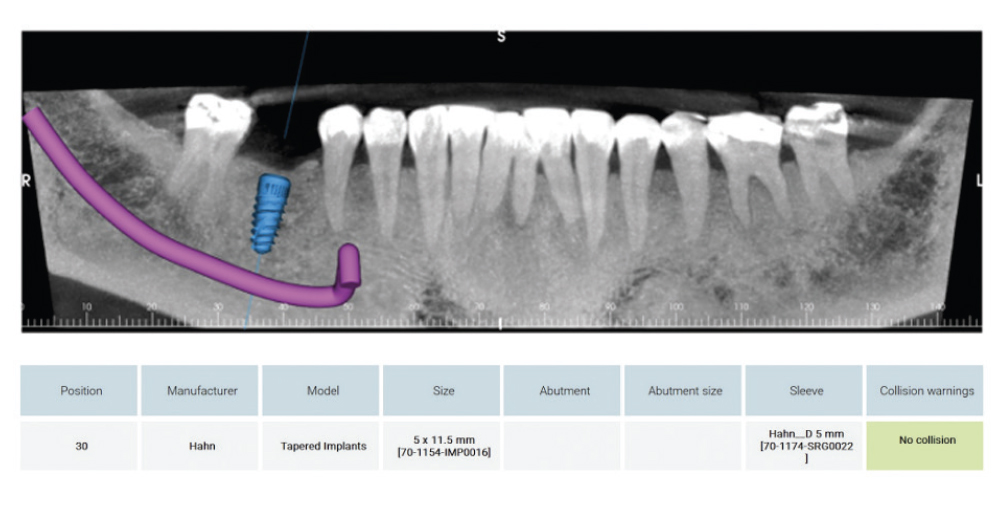

CBCT Scan and Schematics of Proposed Implant and Crown Placement

Figure 3: After a favorable intraoral assessment, a CBCT scan and preliminary reading were performed to confirm that the case was ready for the planning stage. The CBCT was then submitted to Glidewell’s Digital Treatment Planning (DTP) team, including a request that the team plan the case with a Glidewell HT™ Implant and the Glidewell HT Implant Guided Surgical Kit (Glidewell Direct; Irvine, Calif.). The report from DTP included a schematic of the proposed implant and crown placement, as well as the tooth-supported surgical guide. The placement of the crown was evaluated to ensure that it would be harmonious with the rest of the teeth in the arch and that it would provide the patient with proper function. I also ensured the implant followed the long axis of the proposed restoration, and that the screw access hole was in an acceptable esthetic position.

Mapping of the Interior Alveolar Nerve and the Metal Foramen

Figure 4: Mapping of the inferior alveolar nerve and the mental foramen (in purple) allowed an accurate evaluation of the implant placement, ensuring adequate distance from this structure.